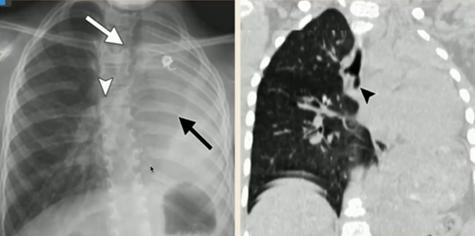

③下呼吸道异物

图23.仰卧位或站立位时右肺过度充气(肺野透亮度高),右侧卧位后透亮度无变化

图24.先天性肺发育不良:(左)左侧无肺组织,肺不张;右侧过度充气,纵隔向患侧偏移;(右)CT可见支气管盲端